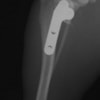

・術後レントゲン

手術前TPA 28.4° が術後TPA 11.7° に矯正されました。

術後TPA計測

手術後